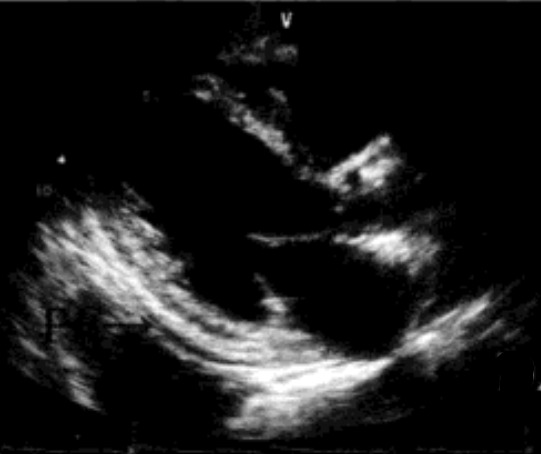

心包积液可以由M型、二维、三维、心腔内超声发现。正常情况下,在心包腔内只有少量的液体,因而只有在后房室沟处可以看见很小的无回声区,该无回声区在舒张末期常常消失,只在收缩期出现。积液也会积聚在斜窦,即左房和大血管之间的潜在腔隙,在这种情况下,左心耳、肺动脉、主动脉周围都会出现液体,仅在这些部位出现的液体可能是正常的。当积液的量增加时,表现为心脏的前方和后方出现无回声区,虽然常规超声心动图无法准确测定心包积液的量,但是无回声区的宽度与心包积液的量明显相关。

少量:仅在左室后壁后方出现无回声区,收缩期和舒张期持续存在,舒张期最深处一般小于1cm,液体量<100ml。

中等量:心脏周围环绕无回声区,左室后壁后方无回声区在1~2cm,右心室前壁无回声区<1cm,液体量在100~500ml。